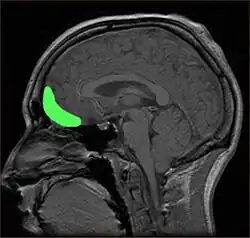

Within the brain, there is some support for the role of the orbitofrontal cortex (OFC) in producing self-conscious emotions, such as shame (Beer, et al., 2003; Leary, 2007; Sturm, Ascher, Miller, & Levenson, 2008). People with damage to the OFC have shown impairments in both the ability to appropriately express self-conscious emotions, such as shame, and in their social behaviour (Beer et al.). In Beer and colleagues' (2003) study, participants with OFC damage were more likely to overshare intimate information on a disclosure task, for example, telling about cheating on their partner, whereas other participants gave more guarded answers, such as being embarrassed when they did not understand a punchline. Those with OFC damage were also less likely to recognise self-conscious emotions on a recognition test than participants without any damage, although there was no difference between the groups in recognising other emotions (Beer et al.). This inability to correctly detect others' emotional responses suggests people with OFC damage may be missing important signals that their behaviour is inappropriate, such as others' embarrassment (Beer et al.). However, since others do not have to be real or physically present for a person to experience shame or the other self-conscious emotions, this suggests damage impairs the ability to correctly infer others' reactions to behaviour (Beer et al.).